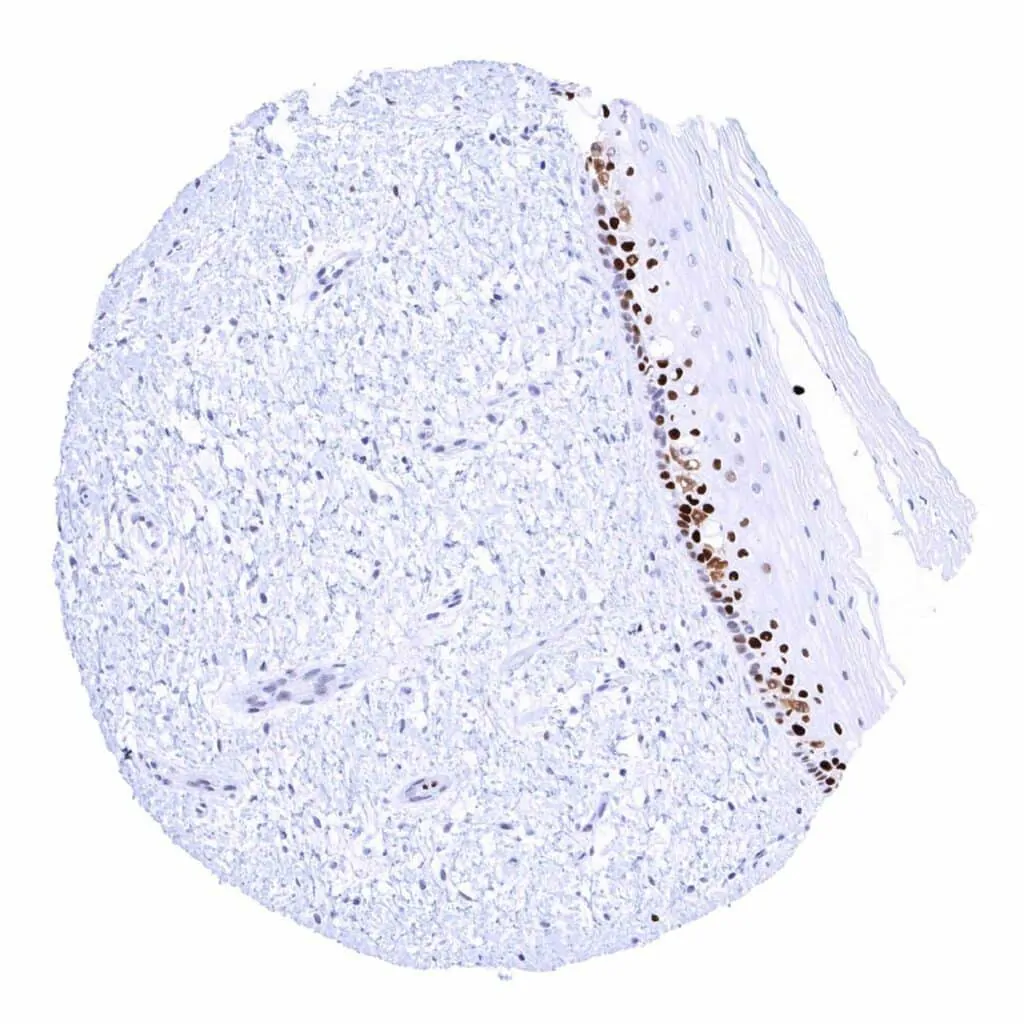

Uterus, ectocervix – The squamous epithelium shows a moderate MCM2 immunostaining of (mostly) suprabasal cells